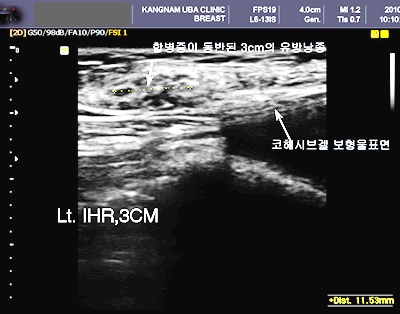

“비단 유방암이 아니더라도 여성에서는 유방낭종이나 섬유선종 등 양성 종양들이 많은 여성들에게서 발견되는데 특히 유방확대를 할 경우 보형물에 의하여 표면으로 올라오면서 이전에는 잘 만져지지 않던 혹들이 많이 만져진다며 불안해 하는 여성들이 많이 있다.

이럴 경우 반드시 유방암 전문의를 찾아서 유방암 검사를 받아야 한다”고 말한다.